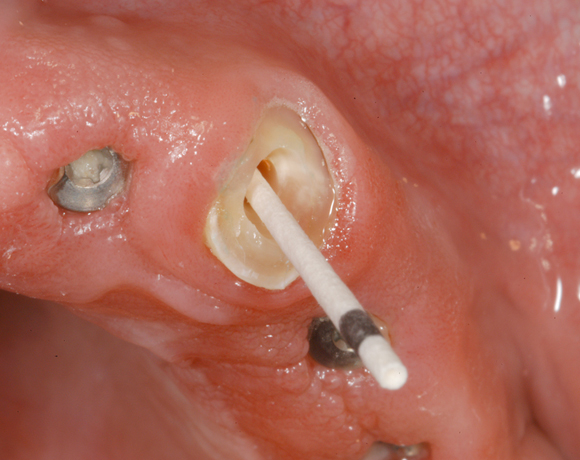

Glasfaserstifte haben den großen Vorteil, dass es Lichtleiter sind, die adhäsiv befestigt werden können. Sie sind metallfrei und haben eine hohe Stabilität.

Im nachfolgenden Patientenfall wird ein Zahn mit einem Stift soweit aufgebaut, dass es möglich wird ihn wieder mit einer Krone zu versorgen.